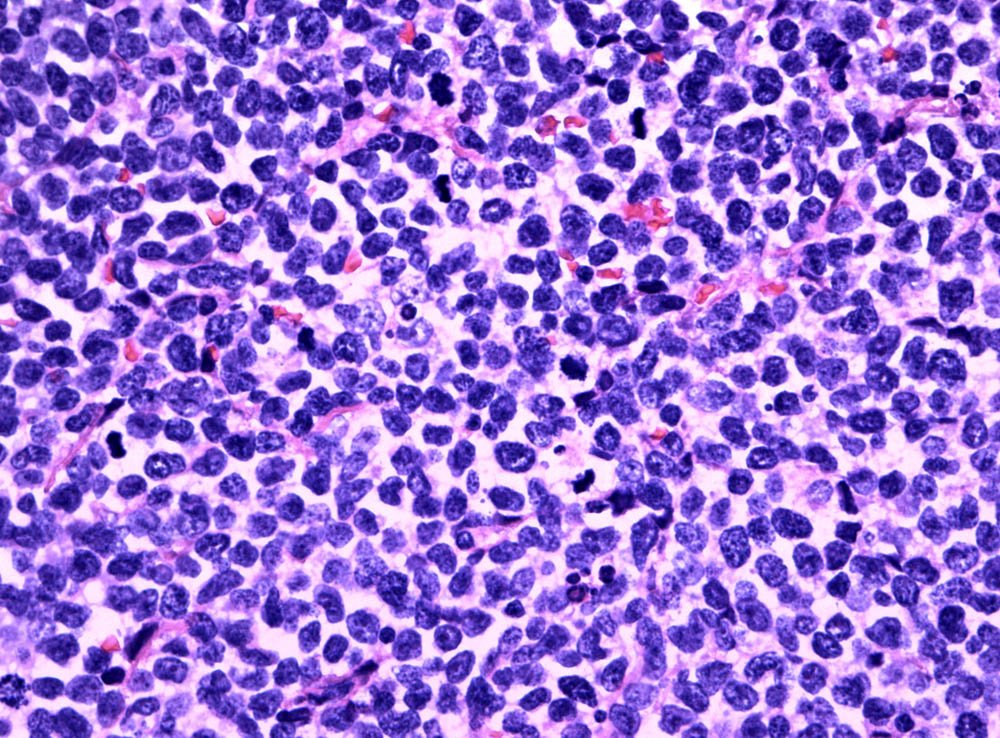

Case: AxillaryMass

Specials to Order:

Final Diagnosis: